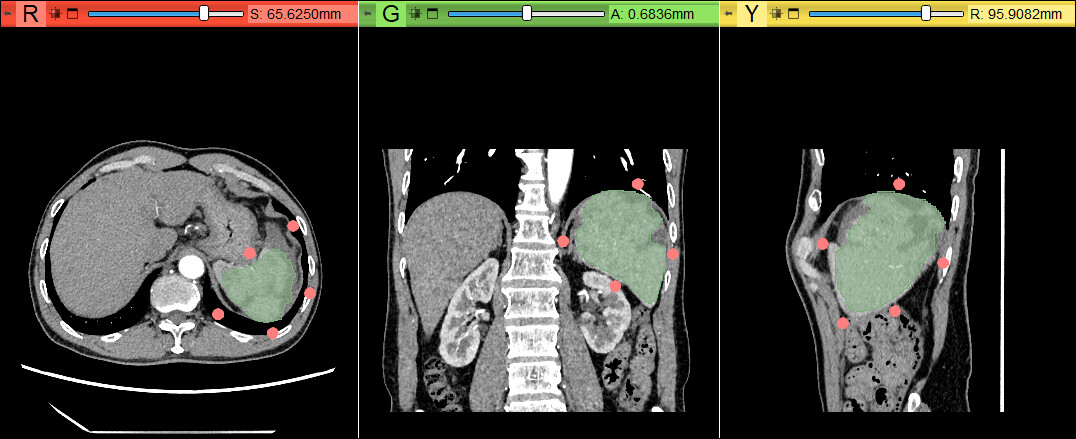

二、Segment from boundary points(DExgtr3D)

首先在Model中选择需要进行分割的组织菜单,再点击基准点,在需要分割的组织周围放置基准点,当放置的基准点足够时,Start由灰色变为彩色,点击后即可自动分割。